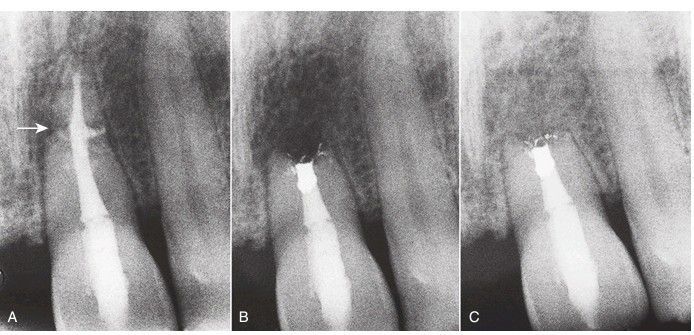

A) Horizontal root fracture (arrow), with failed attempt to treat both segments. (B) The apical segment is removed surgically, and retrograde amalgam is placed. (C) Healing is complete after 1 year.